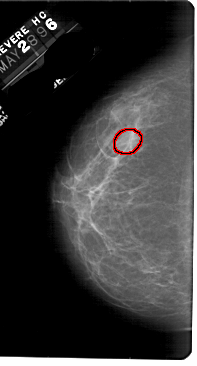

FILE: A_1833_1.LEFT_MLO.OVERLAY

TOTAL_ABNORMALITIES 1

ABNORMALITY 1

LESION_TYPE MASS SHAPE LOBULATED MARGINS OBSCURED

ASSESSMENT 3

SUBTLETY 3

PATHOLOGY BENIGN

TOTAL_OUTLINES 1

BOUNDARY